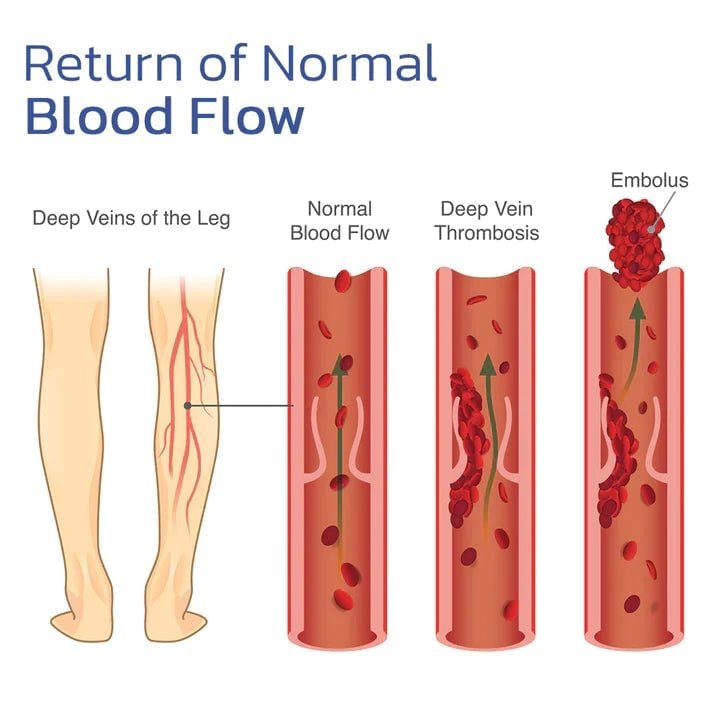

Είναι ρυθμιζόμενη η θερμότητα;

Όχι, η θερμότητα παράγεται φυσικά από τα σωματίδια του τουρμαλίνης σε επαφή με το δέρμα σας.